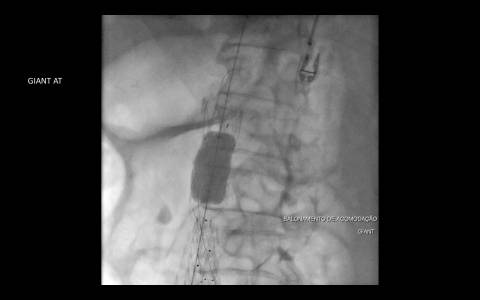

Haja vista a extensa quantidade de comorbidades a cirurgia aberta se fazia de risco muito elevado para o paciente. Este foi então encaminhado para correção endovascular.

O estudo de angiotomografia evidenciou que as artérias iliacas externas e femorais apresentavam-se com muitas calcificações e ponto de estenose mais crítica em artéria ilíaca comum direita. Diante dos achados de imagem, foi optado por endoprotese de aorta abdominal de baixo perfil (Incraft – Cordis).